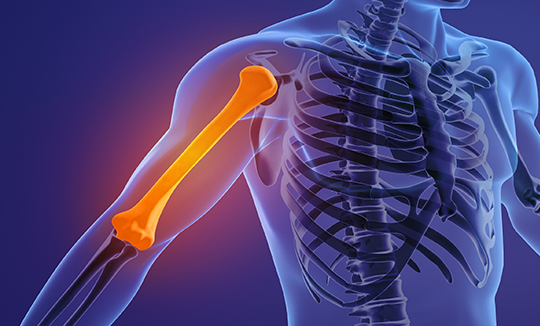

Shoulder Fracture

어깨골절

어깨골절은 상완골, 쇄골, 견갑골 등 어깨관절을 구성하는

뼈가 부러지는 것을 말합니다.

스포츠 활동 증가로 어깨골절 발생도 증가하고 있으며,

골다공증이 있는 경우에는 가벼운 충격에도

골절이 쉽게 발생할 수 있어 주의가 필요합니다.

상완골 골절

상완골 골절은 어깨에서 팔꿈치까지 이르는 긴 팔뼈인 상완골이 부러진 상태입니다.

골절의 발생 위치에 따라 크게 세 가지로 분류됩니다.